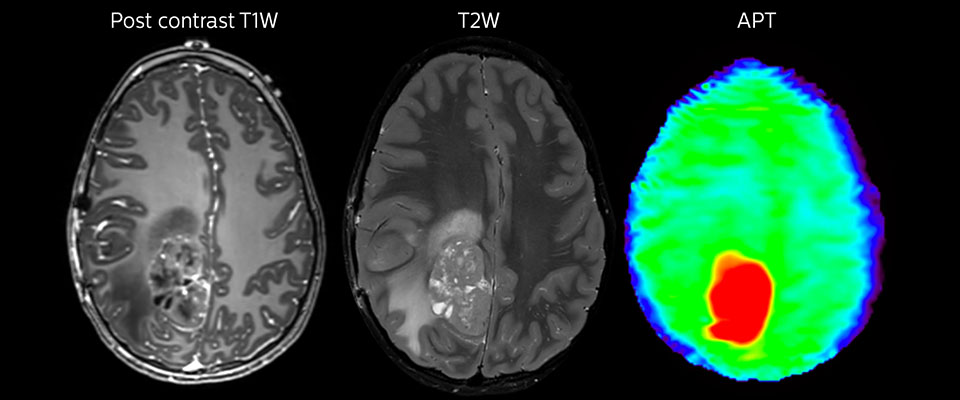

Große metastatische Hirnläsion

Diese 10-jährige Patientin unterzog sich vor 7 Jahren der Resektion eines Ewing-Sarkoms, doch jetzt wurde eine große metastatische Läsion im Gehirn entdeckt. Diese Läsion zeigt deutlich ein erhöhtes APT-Signal.